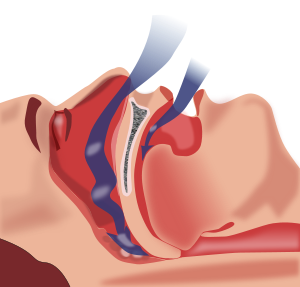

Case Report

J Sleep Disor: Treat Care 2013, 2:4

10.4172/2325-9639.1000123